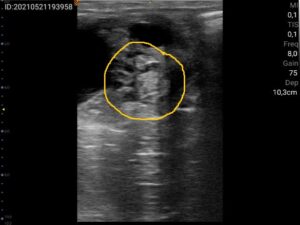

Na meerdere controles bleek Beike geen normale cyclus te ontwikkelen. Matthijs ontdekte een bijzondere en kleine, afwijkende structuur op de eierstok. De eigenaar meldt bovendien dat Beike vervelend gedrag onder het zadel vertoont. Ze verzet zich en is tegen het been. ‘Met al deze symptomen bij elkaar, begon ik te denken dat de merrie een hormoon producerende tumor op de eierstok zou kunnen hebben. Maar dit soort tumoren zijn zeldzaam bij jonge merries en vaak zijn deze tumoren groot, een bal van ongeveer tien tot twintig centimeter in doorsnee. De afwijkende structuur in de eierstok bij de zesjarige Beike was maar vier centimeter groot,’ zegt De Waart.

Om meer duidelijkheid te krijgen over de mogelijke tumor is er bloedonderzoek gedaan. De waardes waren licht afwijkend maar wel passende bij een granulosaceltumor. Dit is een tumor van de eierstokken, welke vaak goedaardig is, maar wel zorgt voor een afwijkende hormoonproductie. De symptomen zijn heel wisselend, sommige merries reageren sterk op de hormonale veranderingen en laten hengstengedrag zien, ontwikkelen geen normale cyclus, en zijn nukkig als ze onder het zadel worden gereden. Samen met de eigenaar neemt Matthijs de beslissing om Beike te laten opereren in een specialistische kliniek: ‘De eierstok met de tumor is opgestuurd naar de afdeling pathologie van de Faculteit Diergeneeskunde om te bepalen of er inderdaad sprake is geweest van een tumor. Uit histologisch onderzoek, dat is onderzoek van weefsel of een orgaan, kwam de bevestiging dat het ging om een hormoon producerende granulosaceltumor’.